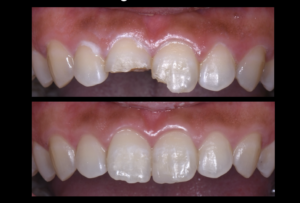

① #8: 破折片をそのまま利用して接着させる。#9: ダイレクトボンディング(コンポジットレジン修復)

結論から言うと①の方針で治療を進めることになりました。なぜなら、一番費用対効果が高いからです。特に、#8に関しては、ご自身の歯をもう一度接着させるだけなので削らずに治療ができ、本来の歯の形態に戻すことができます。もちろん、再度とれてしまうこともリスクとしてはありますが、患者様は開口という歯並びのため、あまり前歯に負担がかからない歯並びをされていました。従って、通常より破折のリスクは低いでしょう。また、露髄もなくレジンセメントと優れた化学的接着が可能なエナメル質が残っているのも一つの要因です。優れた接着力を期待できます。②と③に比べ、かかる費用も安いです。

実際の治療では、ラバーダム防湿後に#8の破折片と歯にサンドブラスティングを施行。リン酸でエッチングをして、第4世代のトータルエッチングシステムを用いて、レジンセメントにて接着させました。#9も通常通り前処理後にレジン充填にて修復しました。切端の特徴的な段差もできるようにデザインしました。